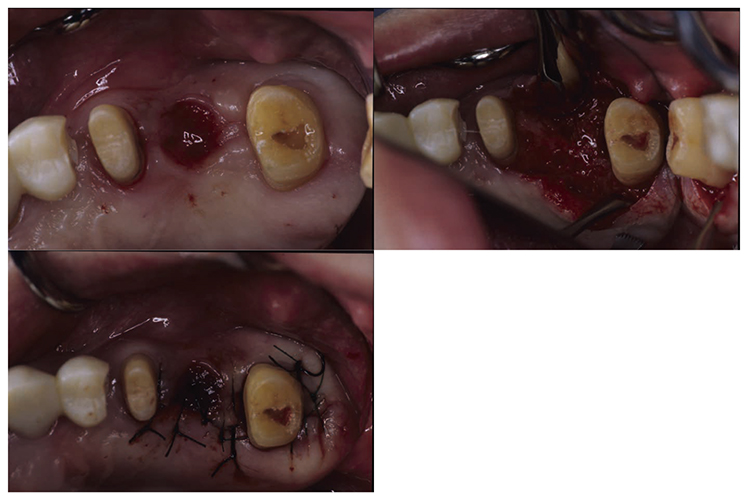

3) Periodontal surgical therapy

At the reevaluation examination after completion of basic periodontal treatment, deep periodontal pockets and grade 2 furcation involvement were observed. Therefore, in April 2010 (age 42), enamel matrix proteins were applied in a procedure for periodontal regeneration (Fig.4),and in June of the same year, gingival flap operation and distal wedge procedure were performed on 27 (Fig.5). For the remaining PD on the lingual side of 36 and 46, due to insufficient keratinized gingiva, the option was to stabilize the condition with SRP.

(Fig.4) Enamel matrix proteins were applied in a procedure for periodontal regeneration in the maxillary left molar (April 1, 2020)

(Fig.5) Gingival flap operation and distal wedge procedure were performed on the maxillary left second molar (June 2010)